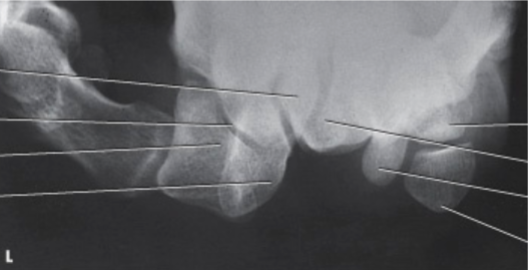

What projection is used in trauma to demonstrate the radial and coronoid process?

axiolateral elbow projection

What is another name for the axiolateral projection?

Coyle’s Method

To view the radial head in an axiolateral elbow projection, how much is the elbow bent?

90 degrees

To view the coronoid process in an axiolateral elbow projection, how much is the elbow bent?

80 degrees

In what position is the hand in for an axiolateral elbow projection?

pronated

How much is the CR angled for an axiolateral elbow projection?

45

Where is the tube angled for an axiolateral elbow projection that shows the radial head?

towards the shoulder

Where is the tube angled for an axiolateral elbow projection that shows the coronoid process?

away from the shoulder

axiolateral elbow (showing radial head)

What is the projection, anatomy and position shown?